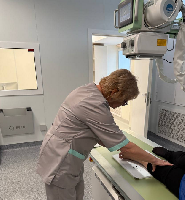

На рабочем месте производится обучение работе на Вашем оборудовании.

Любого доктора можно быстро подготовить как рентгенлаборанта и дать необходимые знания для оценки рентгенограмм.

Изучение проблемы низкого качества рентгенограмм на Вашем оборудовании.